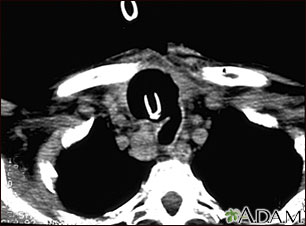

- CT scan of the neck or MRI to determine the size of the tumor.